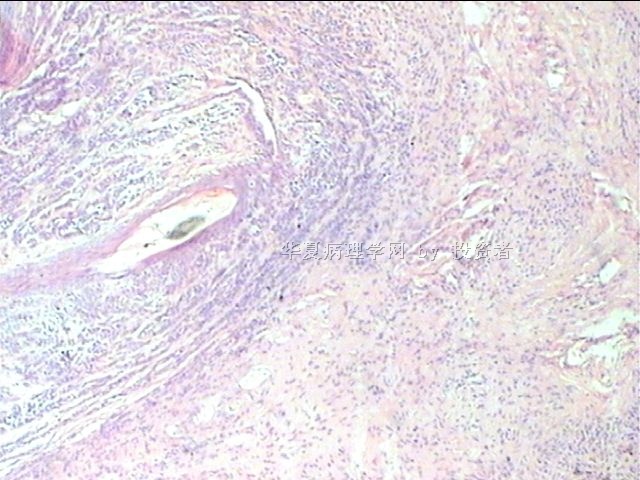

B1634求助皮肤赘生物肿瘤类型

姓    名: ××× 性别:  女 年龄:  25

标本名称: 尾骨下端皮肤赘生物

简要病史:  皮肤赘生物10年余

肉眼检查:  体积1×0.5×0.3cm

×参考诊断

皮内痣

隐约中见似皮内痣。

皮内痣,披着神秘的面纱。

染色太淡,看不清楚。

谢谢各位老师,皮内痣,学习了!

皮内痣可能